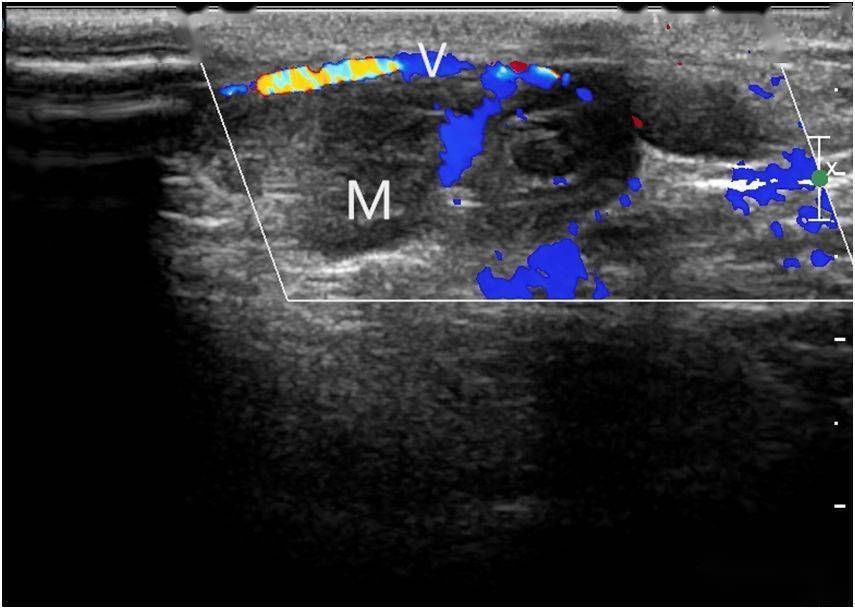

超声典型病例:颈部假性静脉瘤

855x609 - 64KB - JPEG

彩超诊断脾静脉瘤1例

1493x2097 - 1873KB - PNG